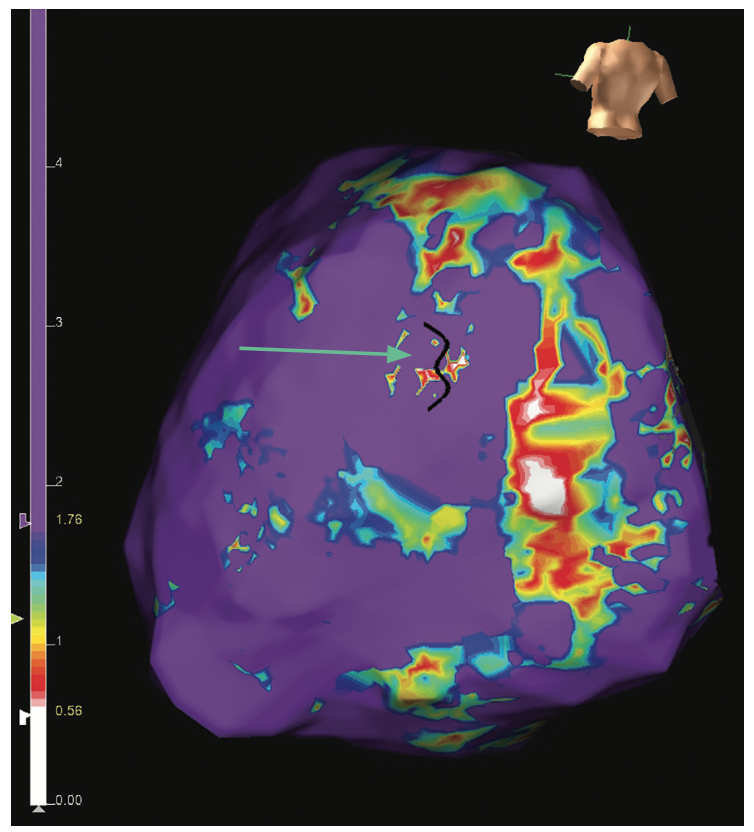

A map analyzing the wave speed can also highlight areas of slow conduction; the white regions are areas of slow conduction and the purple areas are fast conduction. This map can help reveal channels of varying conduction velocity, suggestive of a potential setup for reentry (Figure 4).